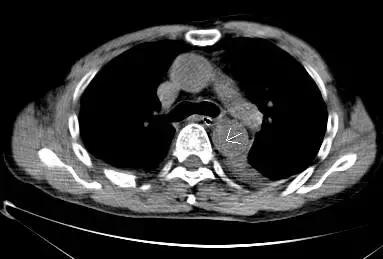

第二招 血管内膜征

正常情况下,主动脉的血管内膜在平扫CT中无法识别,但在某些特殊情况下,主动脉夹层及主动脉壁间血肿的平扫CT中也可以显示,从而帮助诊断。

病例五

平扫CT提示主动脉弓层面及右肺动脉层面均可见主动脉血管腔内的内膜片影(红色箭头所示),CTA显示为A型主动脉夹层。

病例六

平扫CT提示降主动脉内膜片影(白箭头所示),CTA显示为B型主动脉夹层。